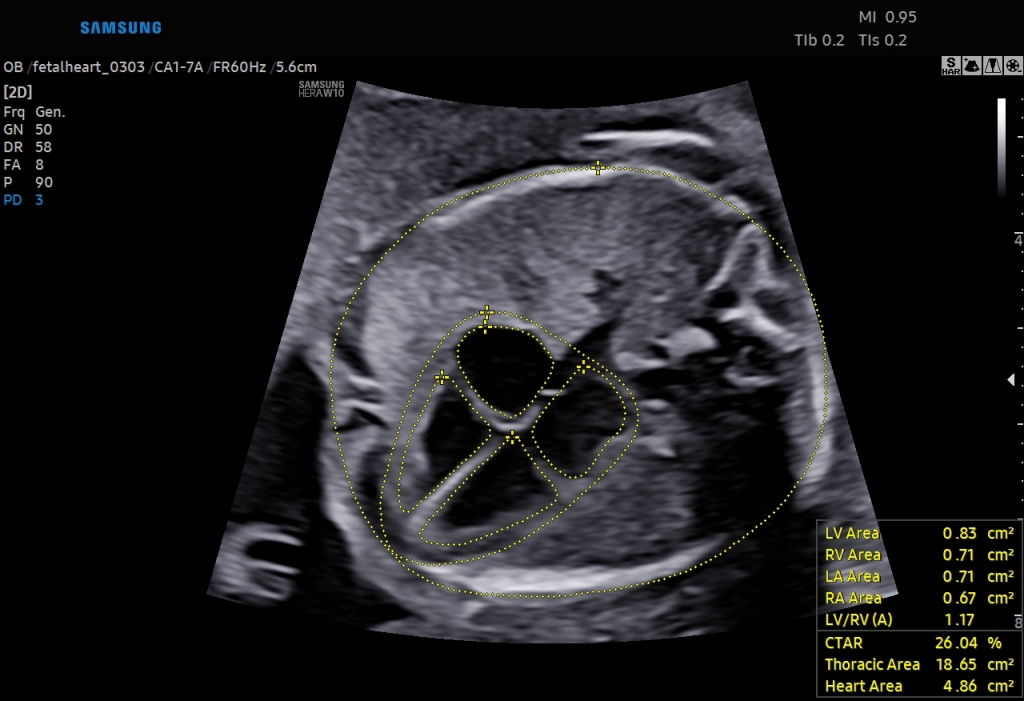

Samsung Presents Clinical Value of Its Enhanced Intelligent Assist Solutions During the Virtual ISUOG World Congress 2021

Samsung Medison, a global medical equipment company and an affiliate of Samsung Electronics, presents the clinical value of its latest deep learning-based diagnostic solutions during the virtual ISUOG (International Society of Ultrasound in Obstetrics & Gynecology) World Congress 2021 held between Oct 15th to the 17th.